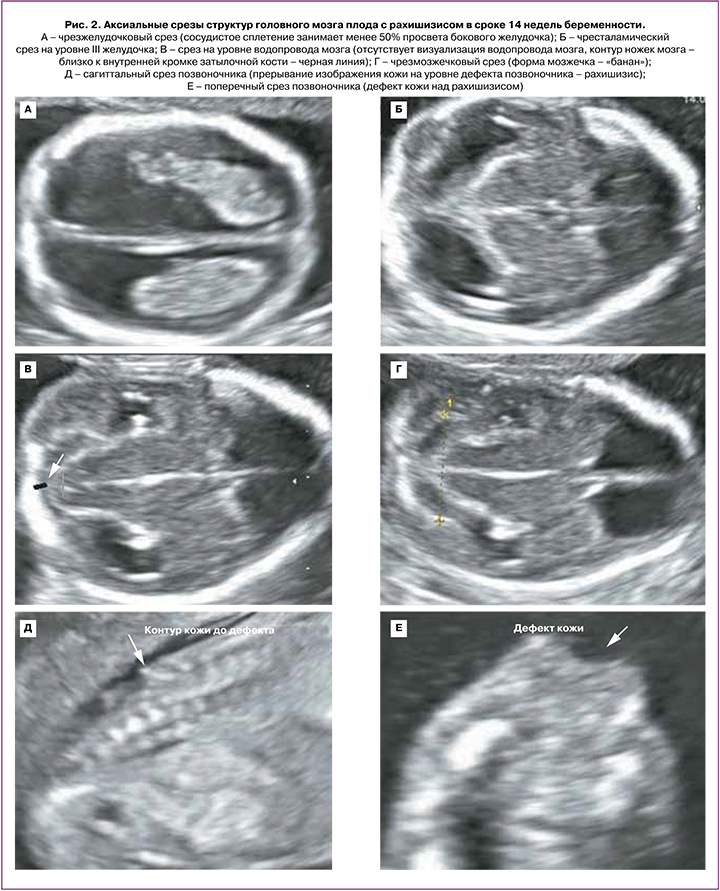

В сроке 12–14 недель у всех 5 плодов были выявлены следующие церебральные особенности: аномальное количество ликвора в боковых желудочках (в 2 случаях – «сухой мозг», в 3 случаях – сосудистое сплетение занимало менее 50% просвета бокового желудочка); сужение/отсутствие визуализации водопровода мозга со смещением его заднего контура к затылочной кости; форма мозжечка – «банан» (рис. 2). Начальный уровень расположения Spina Bifida по отношению к позвоночнику визуализировался с позвонков L2–L3; при этом у 1/5 плодов было выявлено выраженное искривление позвоночника (угол 90°) (рис. 3).

Возможность внутриутробной коррекции Spina Bifida при мальформации Арнольда-Киари II типа привело к внедрению в пренатальную ультразвуковую диагностику расширенной нейросонографии и к разработке новых морфометрических параметров. Оценка структур головного мозга в сагиттальной и коронарной плоскостях в дополнение к аксиальной, позволяет диагностировать порок развития ЦНС уже в I триместре беременности. За последние десятилетия было разработано несколько церебральных эхографических маркеров Spina Bifida в I триместре беременности. Так, еще в 2011 г. группа австралийских ученых – Finn M. et al. выявила, что визуализация смещения заднего края Сильвиева водопровода к контуру затылочной кости является достоверным признаком вклинения задних отделов головного мозга в Большое затылочное отверстие при спинномозговой грыже [11]. Другие исследования показали, что изменение пропорционального соотношения структур: ствол – IV желудочек – Большая цистерна, визуализируемого в средне-сагиттальной плоскости, а именно уменьшение расстояния между задним контуром ствола и затылочной костью, также может говорить о наличии порока нервной трубки [17]. В нашем исследовании обнаружение вышеуказанных маркеров позволило выявить Киари II у 5 пациентов в I триместре беременности.